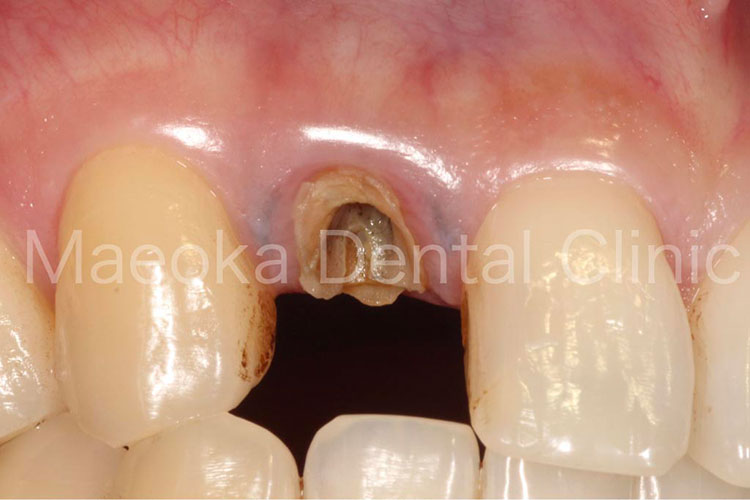

Case5

患者さんは39歳男性の方で、「右の前歯の差し歯が取れたので診て欲しい」という主訴で来院されました。お話を伺うと問題の差し歯は前医に通院中、何度も脱落と再着を繰り返していたとのことでした。

差し歯の土台となっている右上2は歯肉上に健全な歯がなく、現在のままでは被せ物を新たに作っても、歯肉にめり込ませるような形でしか入れられない状態でした。

そこで、患者さんと相談した上で右上2に対してExtrusion(歯を引っ張り上げる処置)を行い、歯肉上に健全歯質を確保した上で被せ物をやり直すこととなりました。前歯ということもあり、薄い仮歯を表面に貼り付けることで審美面に配慮しながら治療を進めました。

クラウンレングスニング(歯肉の整形)も行った上で最終的な被せ物をセットして治療を終えています。

現在のところ一度も脱離はなく、良好な経過が得られています。

今後はメインテナンスにて噛み合わせの変化も含めてチェックを行っていきます。

治療前(右上2)

治療後(右上2)

治療中(Extrusion装置)

治療中(歯肉整形後)